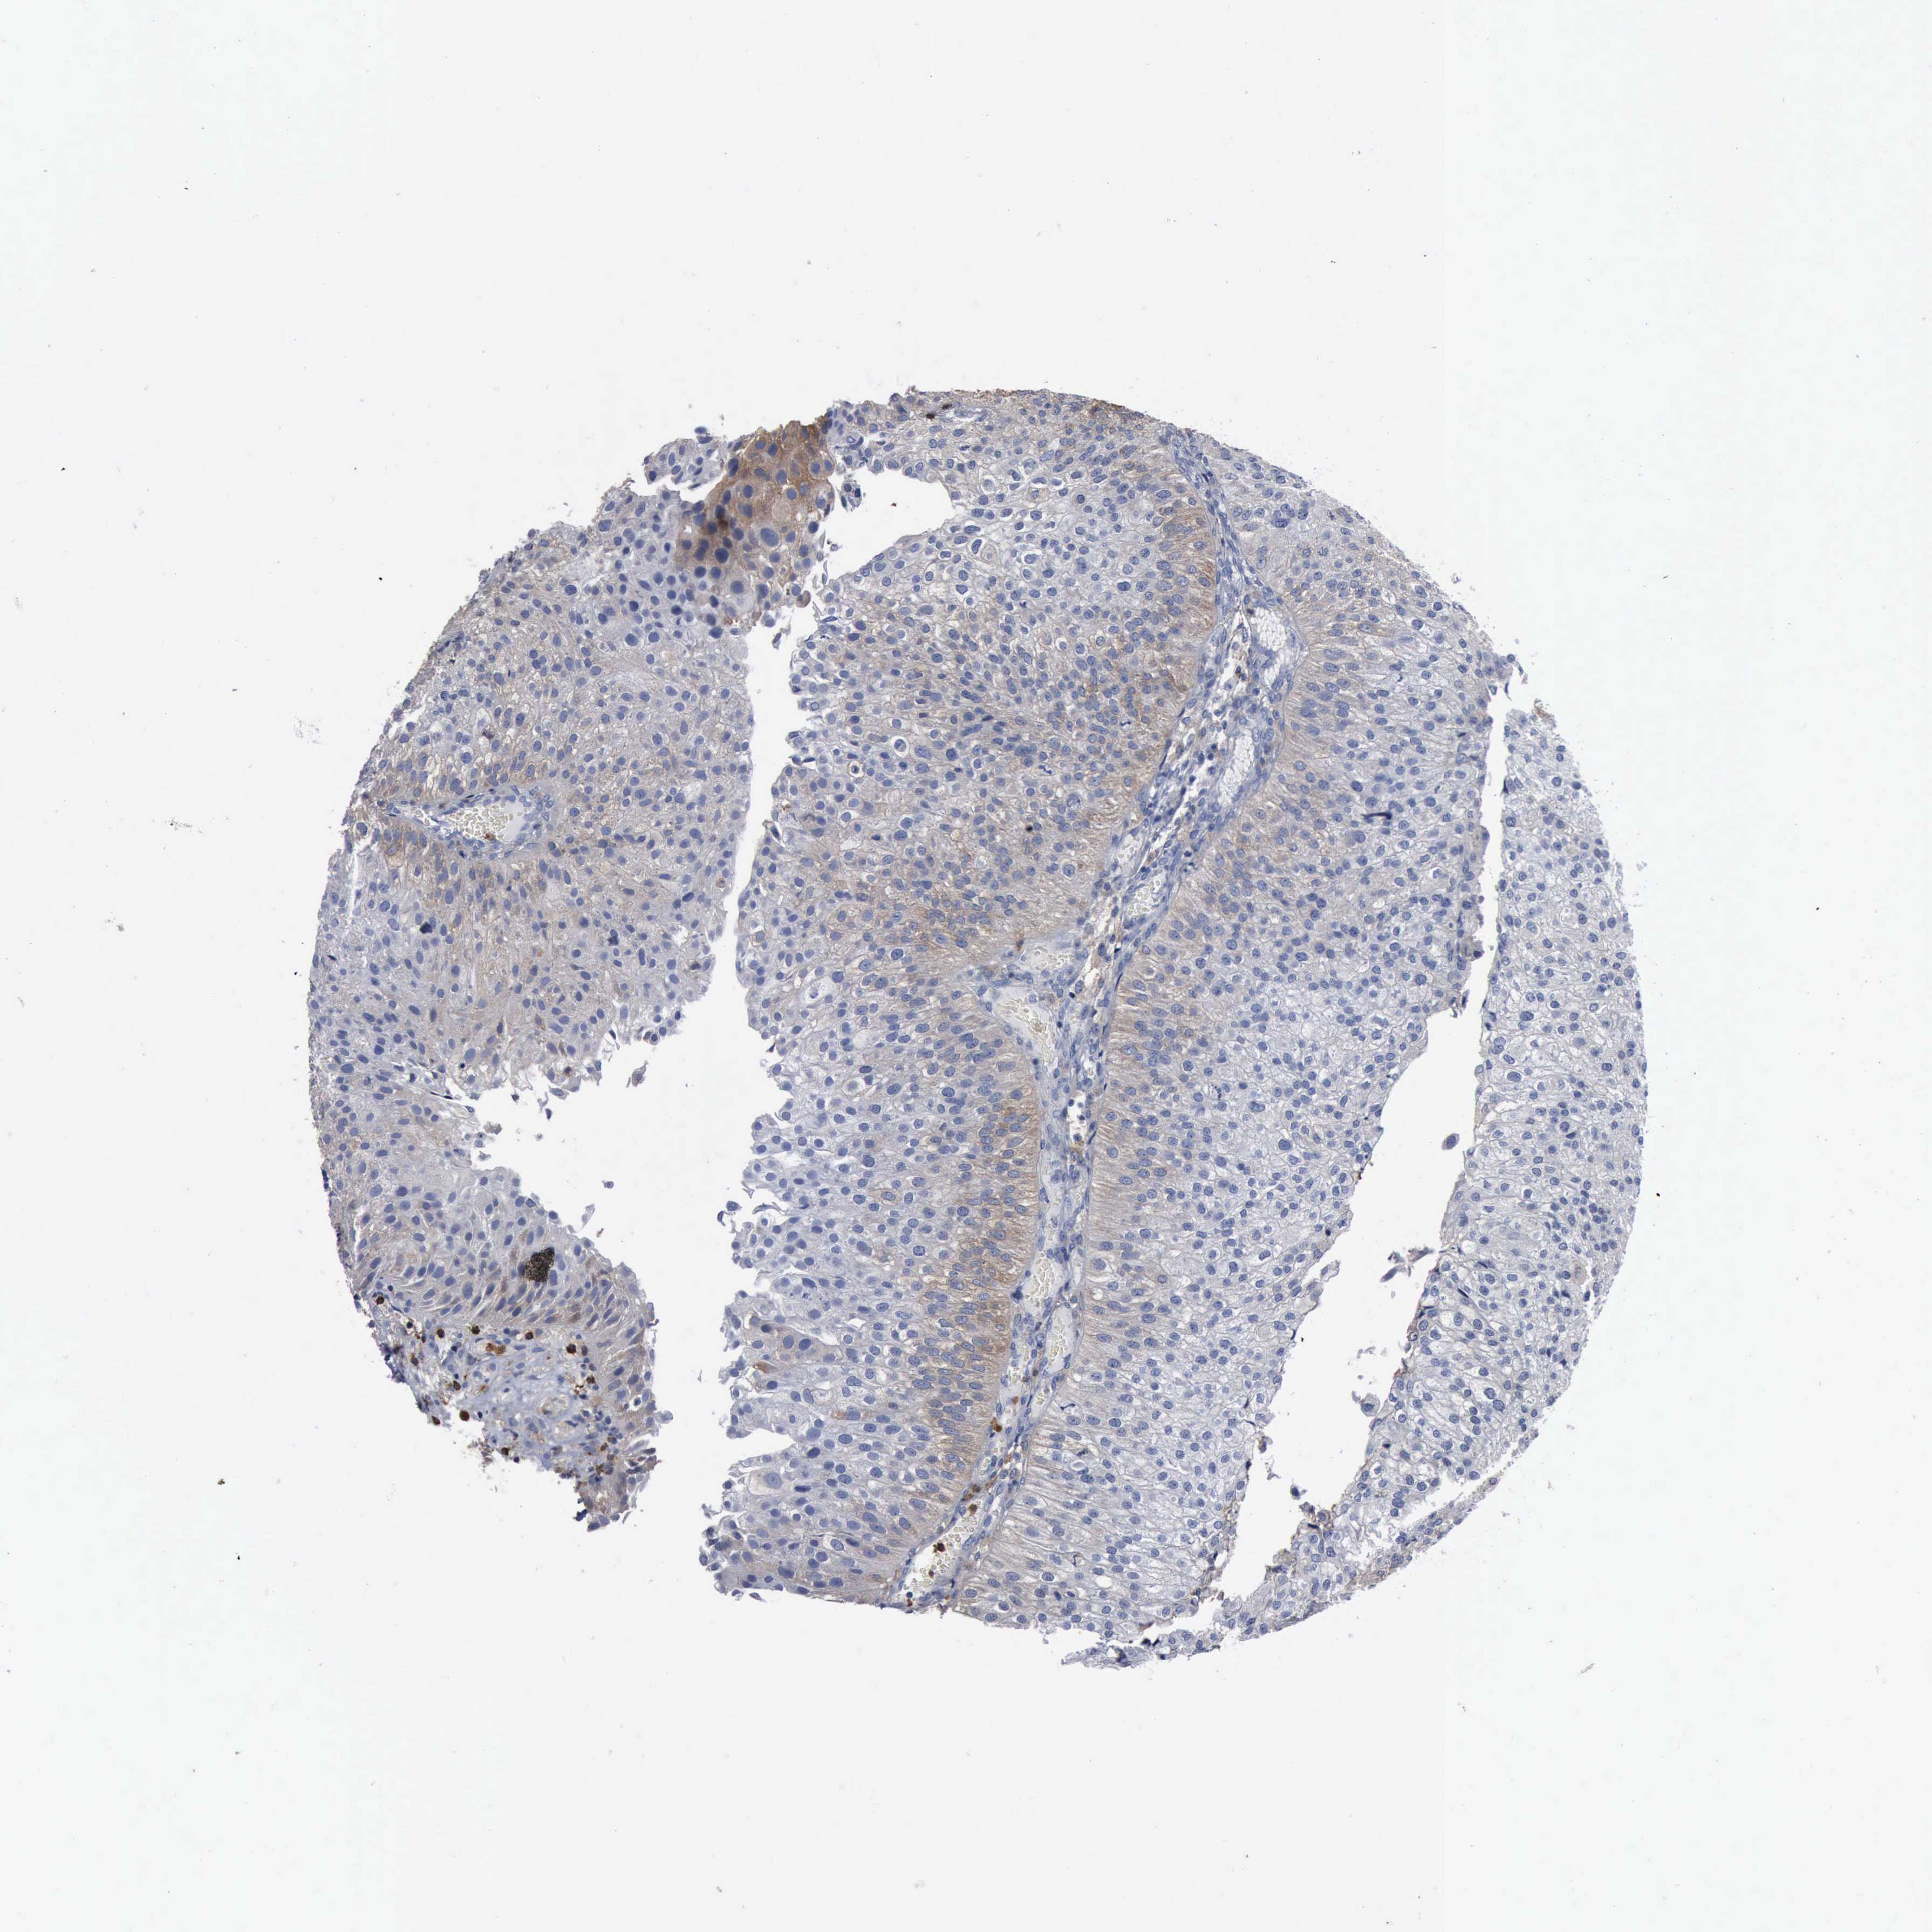

UROTHELIAL CANCER - Protein expressioni

A mouse-over function shows sample information and annotation data. Click on an image to view it in a full screen mode. Samples can be filtered based on level of antibody staining by selecting one or several of the following categories: high, medium, low and not detected. The assay and annotation is described here.

Antibody stainingi

Antibody staining in the annotated cell types in the current human tissue is reported as not detected, low, medium, or high, based on conventional immunohistochemistry profiling in selected tissues. This score is based on the combination of the staining intensity and fraction of stained cells.

Each image is clickable and will lead to virtual microscopy that enables deeper exploration of all samples and also displays staining intensity scores, fraction scores and subcellular localization as well as patient and tissue information for each sample.

Antibody HPA000962

Antibody HPA004119

Staining

High

Medium

Low

Not detected

Intensity

Strong

Moderate

Weak

Negative

Quantity

>75%

75%-25%

<25%

None

Location

Nuclear

Cytoplasmic/membranous

Cytoplasmic/membranous,nuclear

Urothelial carcinoma, Low grade